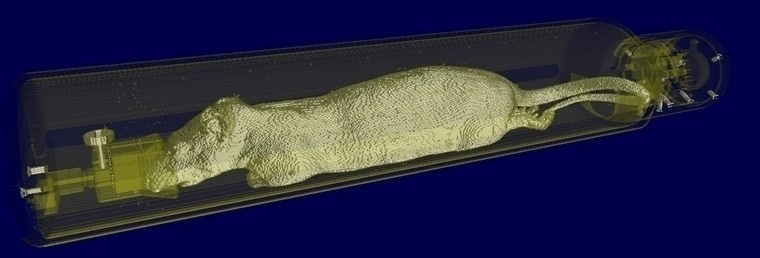

Automatic MR-based Attenuation Correction (AC), calculating for animal cradle, MRI RF coil, and full animal body. Image Credit: Bruker BioSpin Group